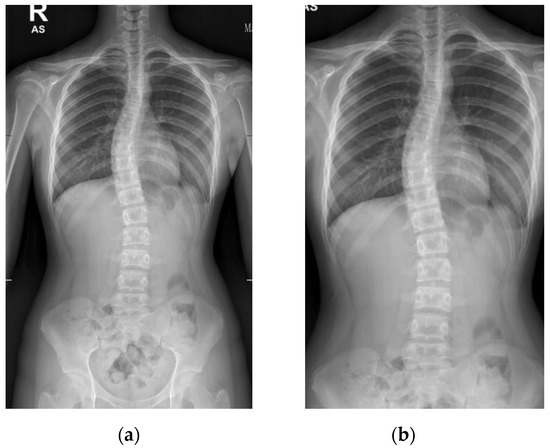

Patients with AIS who attended the scoliosis clinic at Pantai Jerudong Specialist Centre from 1 November 2018 to 4 September 2020 were identified from the institution’s scoliosis database. These patients had standard standing anterior-posterior X-rays showing cervical vertebra level 7 to the femoral heads and the entire rib cage from right to left as part of routine clinical management. The X-ray images were retrieved from the institution PACS, anonymized, and exported as a JPEG format image, as shown in Figure 2. The CA for each X-ray image was measured by (1) two neurosurgeons (Observer 1 specializes in scoliosis; Observer 2 does not), who were blinded to each other and the ACAMM, using the in-built function in the PACS and (2) the ACAMM.

Figure 2.

Examples of standard X-ray images exported from the PACS: (a) CA < 10°; (b) CA 10° to 25°; (c) CA > 25° to 40°; (d) CA > 40°.